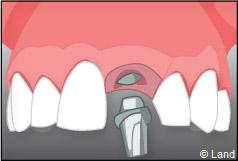

L’implant est placé dans l’os le plus souvent par vissage et doit avoir une liaison forte avec l’os. Le praticien replace alors la gencive et pose des points de suture.

Exemple d’un implant unitaire pour remplacer une dent antérieure manquante.

Pose des piliers prothétiques et des 3 couronnes scellées.